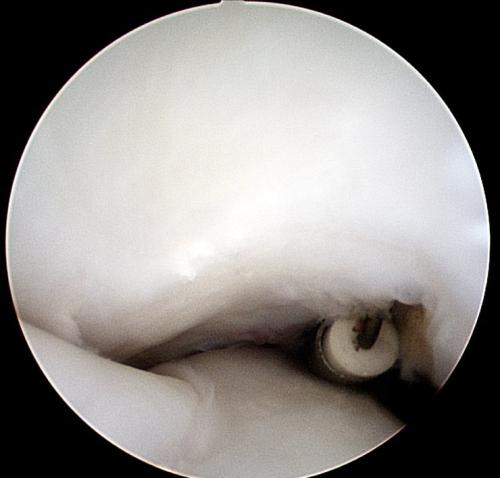

A rehabilitation program will be provided for your horse. This may also include suggestions for post-surgical treatments. For example, it is routine to perform Hyaluronic acid/corticosteroid injections at 2 weeks post surgery following arthroscopic chip/fragment removal. When there is substantial soft-tissue or cartilage injury, we often recommend biologic therapies.